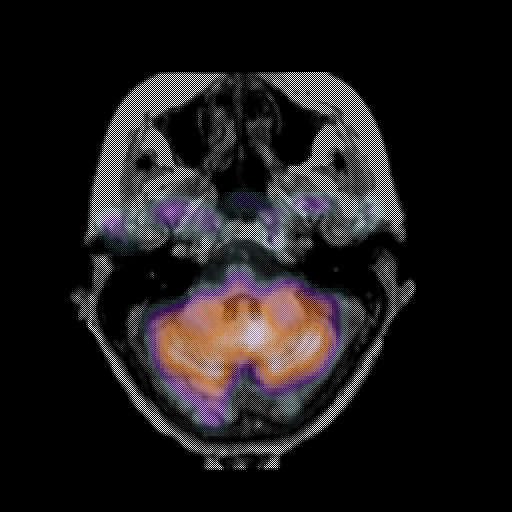

overlay: Slice 12

Slice 12

MRCBFCBF with

T1PDT2T1PDT2